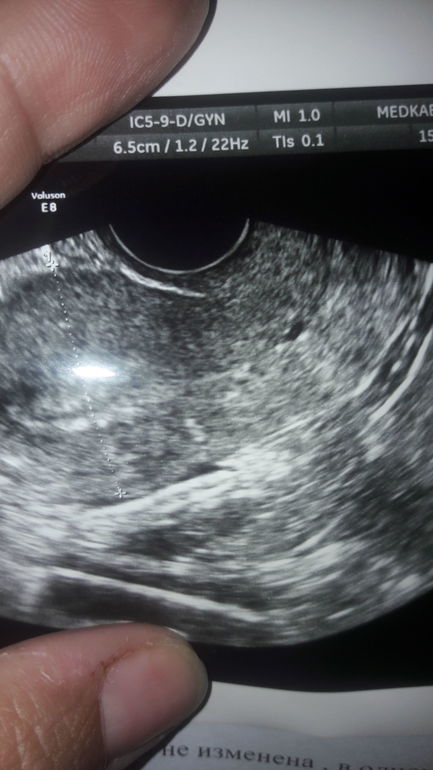

Может кто-нибудь разбирается сегодня сделала УЗИ и на фото увидела какое-то пятнышко.

узист сказала что нет кист не каких. Я сначала просто не заметила пришла домой разглядела

Наботовы кисты, это вариант нормы, практически. У каждой второй есть, просто результат закупорки протока наботовой железы. Здесь судя по локализации похоже, что это в шейке матки, анэхогенное мелкое, однозначно киста. Это никак не связано с кистами яичников, о которых вы, вероятно, говорите.

Вообще же, лучше по этим снимкам не пытаться ничего найти самостоятельно,не забивать себе голову ерундой